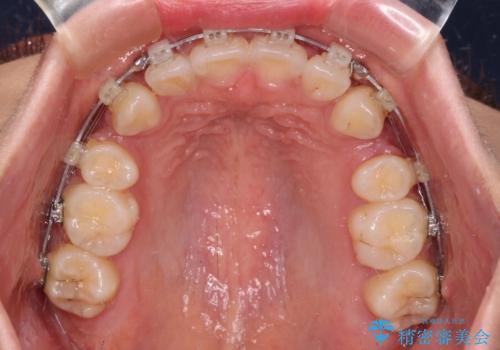

- クリアブラケット

口元の突出感を改善するため、上下左右第一小臼歯4本の抜歯を行い、ワイヤー装置による矯正治療を行うこととしました。

舌の突出癖により上下前歯は非接触であり、非常に前方に飛び出している状態でした。